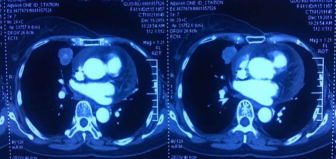

2016.12:28×27cm;2017.05:21×13cm;2017.11:21×13cm;2018.10: 25×18cm。

2018年12月,疾病再次进展。转移灶大小:25×27mm。

右肺中叶内侧段结节25×27mm,较前增大纵膈、右肺门多发增大淋巴结